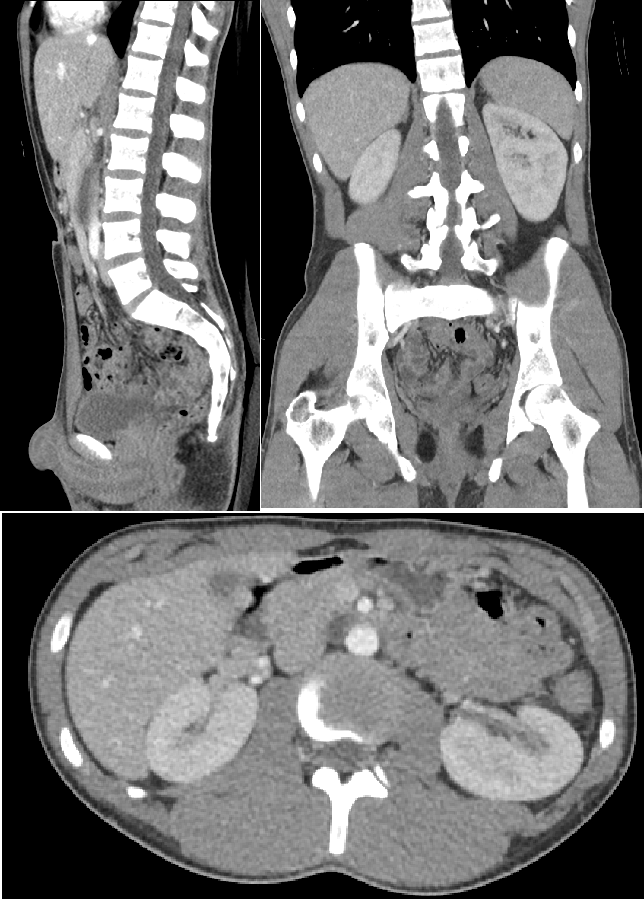

CT는 인체를 360도로 회전하면서 X-선관으로부터의 방사선이 발생되어 피사체를 투과한 감약데이터를 반대편 detector가

획득하며 디지털 신호로 변환, 그 정보를 컴퓨터에서 수학적인 연산과정을 거쳐

우리가 원하는 횡단면(2차원)의 해부학구조를 영상으로 표현해 줄 수 있습니다.

1. X선속은 촬영부위의 단면만 통과함으로 재구성 영상에는 목적 단면(slice) 이외의 정보는 포함되지 않으며, 진단 목적 부위의 다중 단층(multislice)영상에 대하여 2차원적 평면영상 또는 3차원, 4차원적인 체적(volume)영상을 관찰할 수 있다.